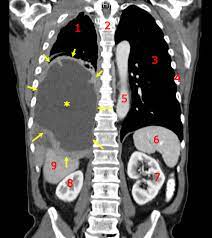

Small Cell Carcinoma Wikipedia from upload.wikimedia.org The lung cancer symptoms in men when diagnosed at initial stage make treatment easy. This growth can spread beyond the lung by the process of metastasis into nearby tissue or other parts of the body. Lung cancer typically doesn't cause signs and symptoms in its earliest stages. If certain symptoms occur or persist, however, a doctor should be seen for further evaluation. A tumor site located in the lung tissue or subpleural: Continue reading to find out more about lung cancer symptoms, what to watch out and listen for. Unfortunately, every complaint or symptom of cancer can be some cancers occur more frequently in certain age groups. In rare instances, patient can even present with digestive symptoms in the absence 22.